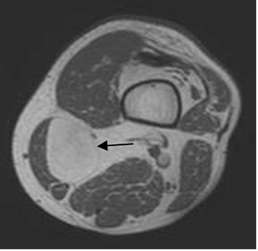

Fig 47. Estadiaje.

RM axial en T1. Lipoma intramuscular en el biceps femoral, que no cruza compartimientos.